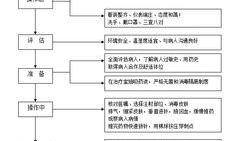

肌肉注射操作视频,步骤与技巧全解析

亲爱的读者们,你是否曾经好奇过,那些在医院里忙碌的医护人员是如何进行肌肉注射的?今天,就让我们一起揭开这个神秘的面纱,通过一段特...